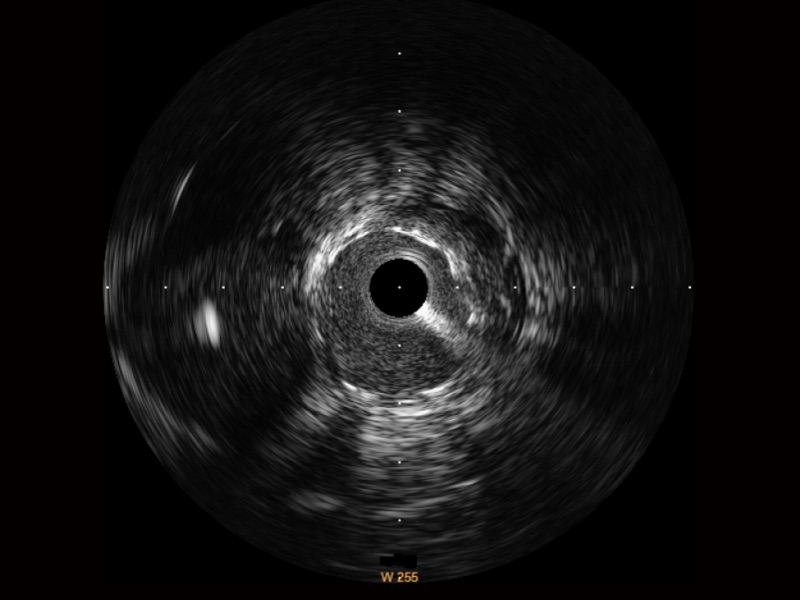

传统IVUS图像

对比传统IVUS导管成像,1xBET宽频IVUS图像的近场支架梁显影更细腻,远场中膜外血管仍清晰可辨,兼顾远中近,兼顾分辨力与穿透深度